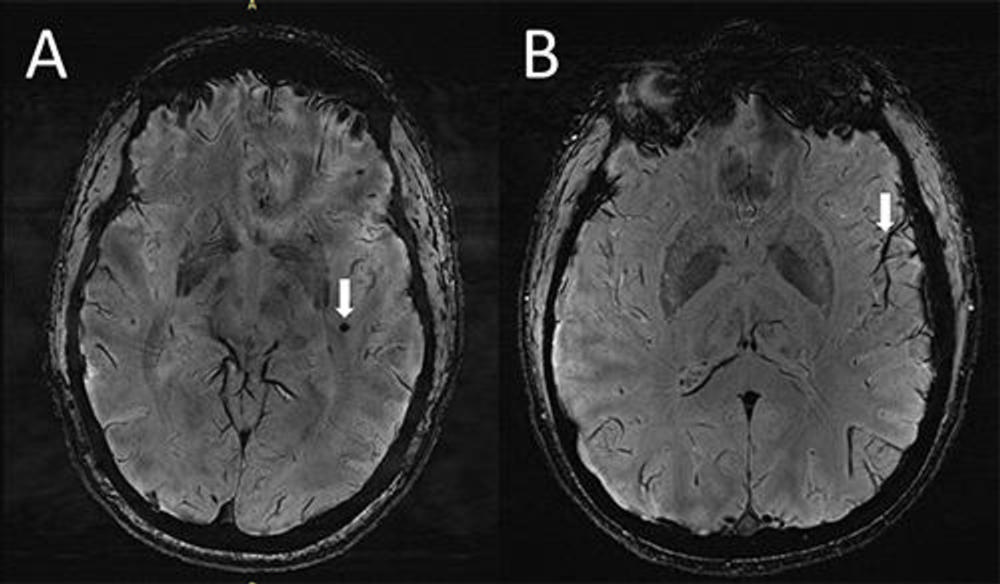

Figure 1. (A) Cerebral microbleeds (CMB) visualized as round, dark lesions (arrow) on SWI sequence in the left temporal lobe in a migraine case with aura. (B) Asymmetry in the appearance of the cortical vessels is more prominent on the left side (arrow) ipsilateral to the CMB.